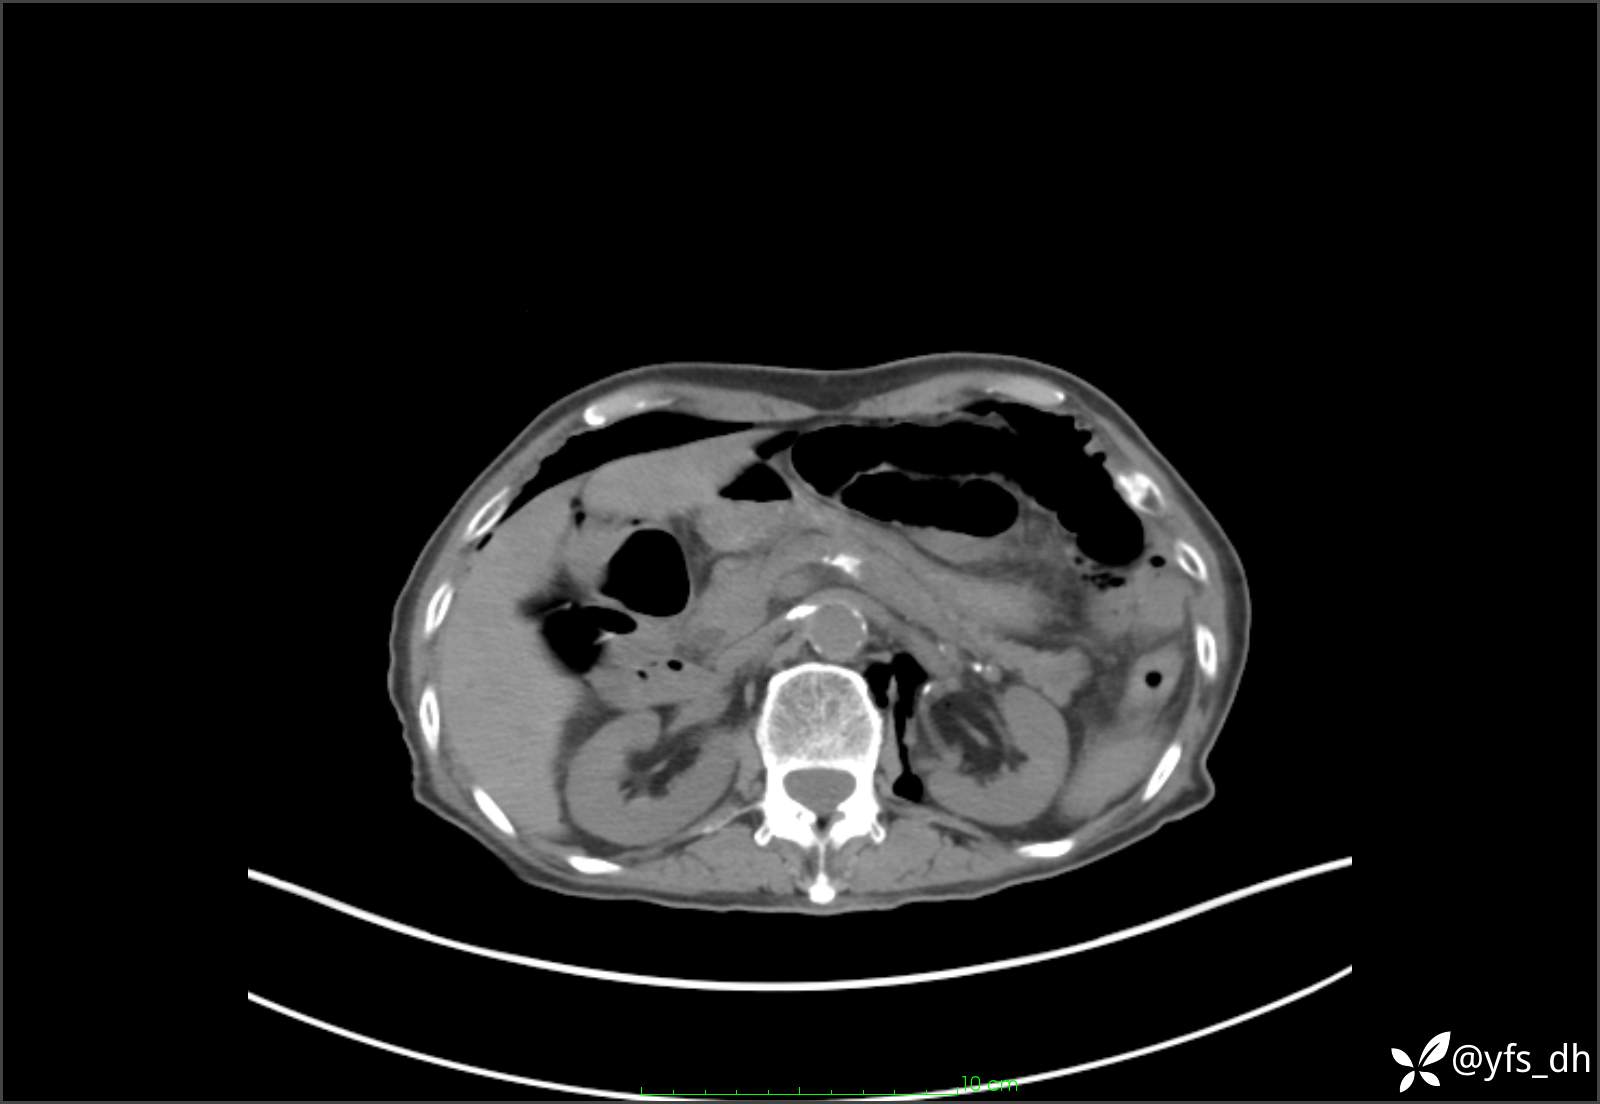

1.简要病史:患者4天前突发上腹部疼痛不适,但可以忍受。3小时前饭后突然加重,不能忍受后就诊。

2.简要手术记录:术中见腹盆腔大量肠液及粪便,乙状结肠中下段见一约3cm的破口。